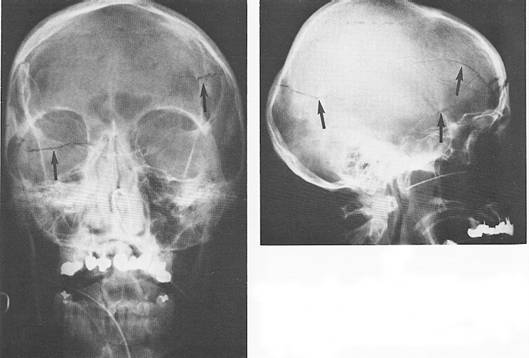

Radiografic se pot constata:

Fisuri craniene

Fracturi nedenivelate (liniare, cominutive, disjunctii suturare, f 656b14g racturi-disjunctie);

Fracturi denivelate (evulzive, cu extruzie si depresive, cu infundare);

Fracturi complexe (cranio-otice, cranio-sinusale, etc).

Fig. 98 – Fractura de bolta caraniana fronto-parietala stanga si parieto-temporo-occipitala dreapta